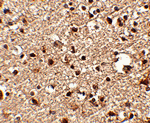

图片:

Immunohistochemistry of JPH4 in human brain tissue with JPH4 antibody at 2.5 ug/mL.